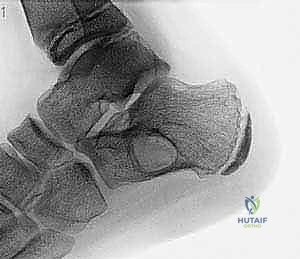

- تورم وانتفاخ ملحوظ: بسبب طبيعته المتمددة، قد يلاحظ المريض أو الأهل كتلة صلبة أو انتفاخاً محسوساً تحت الجلد، خاصة في العظام السطحية مثل القصبة.

- تحدد الحركة: إذا كان الكيس قريباً من المفصل.